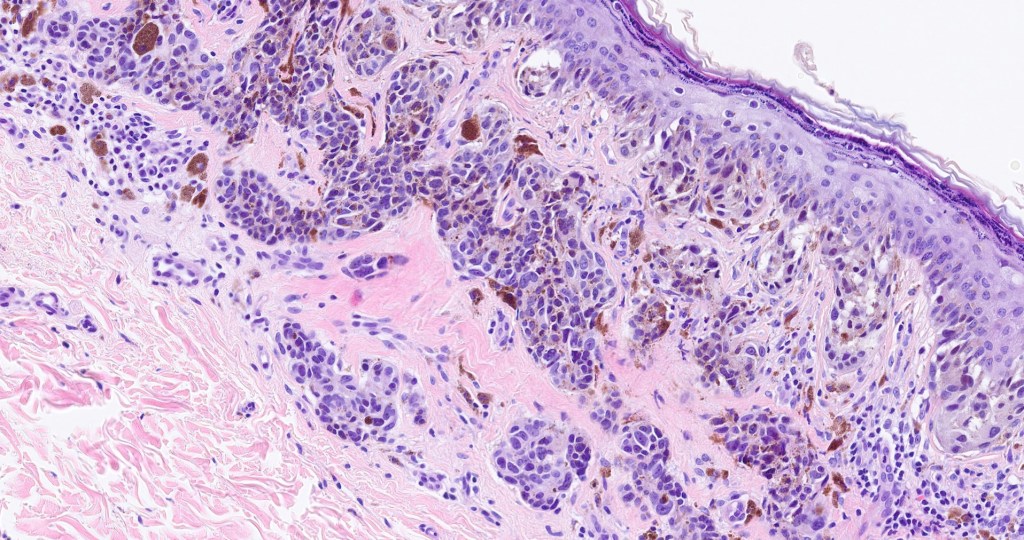

Nevi presenting in the genitalia, inguinal region, umbilicus, axilla and breast may show considerable atypia. They should be readily recognised, often at scanning magnification but may be misdiagnosed as melanoma if the age of the patient and site of the lesion are not taken into account. So-called atypical acral nevus, ear & scalp nevi are covered in separate blogs.

•Atypical genital nevus- vulva & adjacent skin of young women (labium majus>mons pubis>labium minus>clitoris

Histological features

•Junctional/compound

•Large dyscohesive nests with retraction artifact, not restricted to the tips of the epidermal ridges

•Bridging common, often over multiple rete ridges

Most important is melanoma. Distinction is best afforded by the site of the nevus and the patient’s age. Vulval melanoma is generally a tumor of the elderly. Atypical genital nevus occurs in girls and young women.